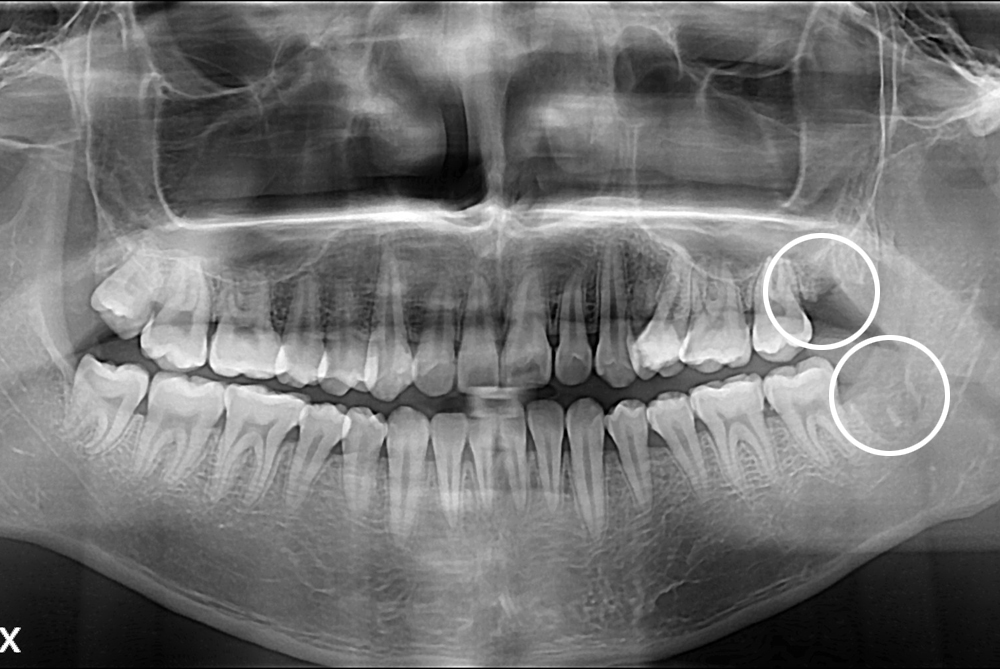

[사랑니] 난발치 사랑니 발치

치료전 : 2017-06-13